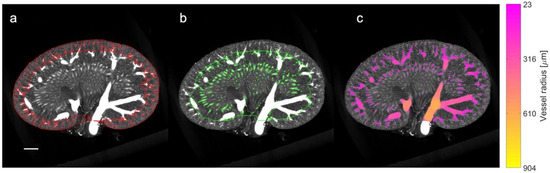

Figure 3.

µCT processing and density analysis. The coronal slice of a µCT scan is portrayed from a 22-week-old lean Zucker rat with the following: (a) the cortex defined by red borders and the mask of small vessels included in the cortical vascular density; (b) the medulla defined by the green border and the mask of small vessels included in the density analysis for the medulla region (note the exclusion of the large segmental and arcuate vessels); and (c) colored voxels representing the full vessel segmentation and the subsequent vessel radius estimation. The color indicates the local vessel radius in accordance with the colormap to the right. Size bar: 2 mm.

The density of the vessel structures was estimated separately for the cortical (Figure 3a) and medullary regions (Figure 3b) using MATLAB and calculated by taking the ratio of the vessel volume (within the region) to the full volume of the region. The analysis excludes the influence of the larger vessels, i.e., the renal artery and vein, the segmental vessels, and the arcuate vessels. This was facilitated by thresholding the estimated vessel radius map to divide the vessel segmentation into ‘small’ and ‘large’ vessel masks (Figure 3c). For the cortex region the threshold was set to a vessel radius of 10 voxels (approx. 230 µm). Similarly, for the medulla region, the threshold was set to 6 voxels (approx. 140 µm). The region of large vessels was then removed to calculate the density.

A quantitative and qualitative assessment of µCT was performed to substantiate our SRUS findings. The full volume of the µCT scans of six rats (a randomly selected subset: an LZR and a ZDF rat from each age group) were processed using ITK-snap (version 3.8.0) with the following two steps: (1) delineation of the kidney boundary and the cortex-to-medulla boundary, and (2) segmentation of the vessel structures and estimation of the local vessel radii [39]. The inner and outer medulla were combined for the µCT measurement; thus, the segmentation was performed differently than on the SRUS images, as the renal cortex was our primary focus and the segmentation on the µCT images was time-consuming. Three people completed the segmentation, two of them blinded to the type of rats to minimize performance bias. The third person could not be blinded as she was the primary investigator of the study.

The anatomical division of the kidney into the cortex and medulla regions was obtained through the following three steps. Firstly, a mask separating the kidney from the background was generated using a semi-automatic threshold-based region-growing algorithm. Manual editing was carried out when needed, e.g., to create a smooth closing at the hilum. Secondly, a mask delineating the inner part of the cortex at the arcuate vessels was created manually. In practice, approximately every fifth coronal slice was segmented using a polygon tool. The segmentation in the remaining slices was filled using label interpolation. Finally, a third mask representing the cortex region was created by ‘subtracting’ the medulla from the entire kidney mask. In the second step, an intensity threshold was manually set to segment all the vascular structures. The threshold was tuned for each scan to obtain a threshold that neither included the area between vessels (too low) nor excluded too many vessels (too high). Afterward, the local radius of the segmented vessels was estimated using the Porespy Python library [40].

The vascular density in the CO and combined IM and OM of three ZDF rats at ages 12, 22, and 40 weeks was consistently lower compared to that of three age-matched LZRs (Figure 10). Additionally, the cortical vascular density appeared to be decreasing with age.